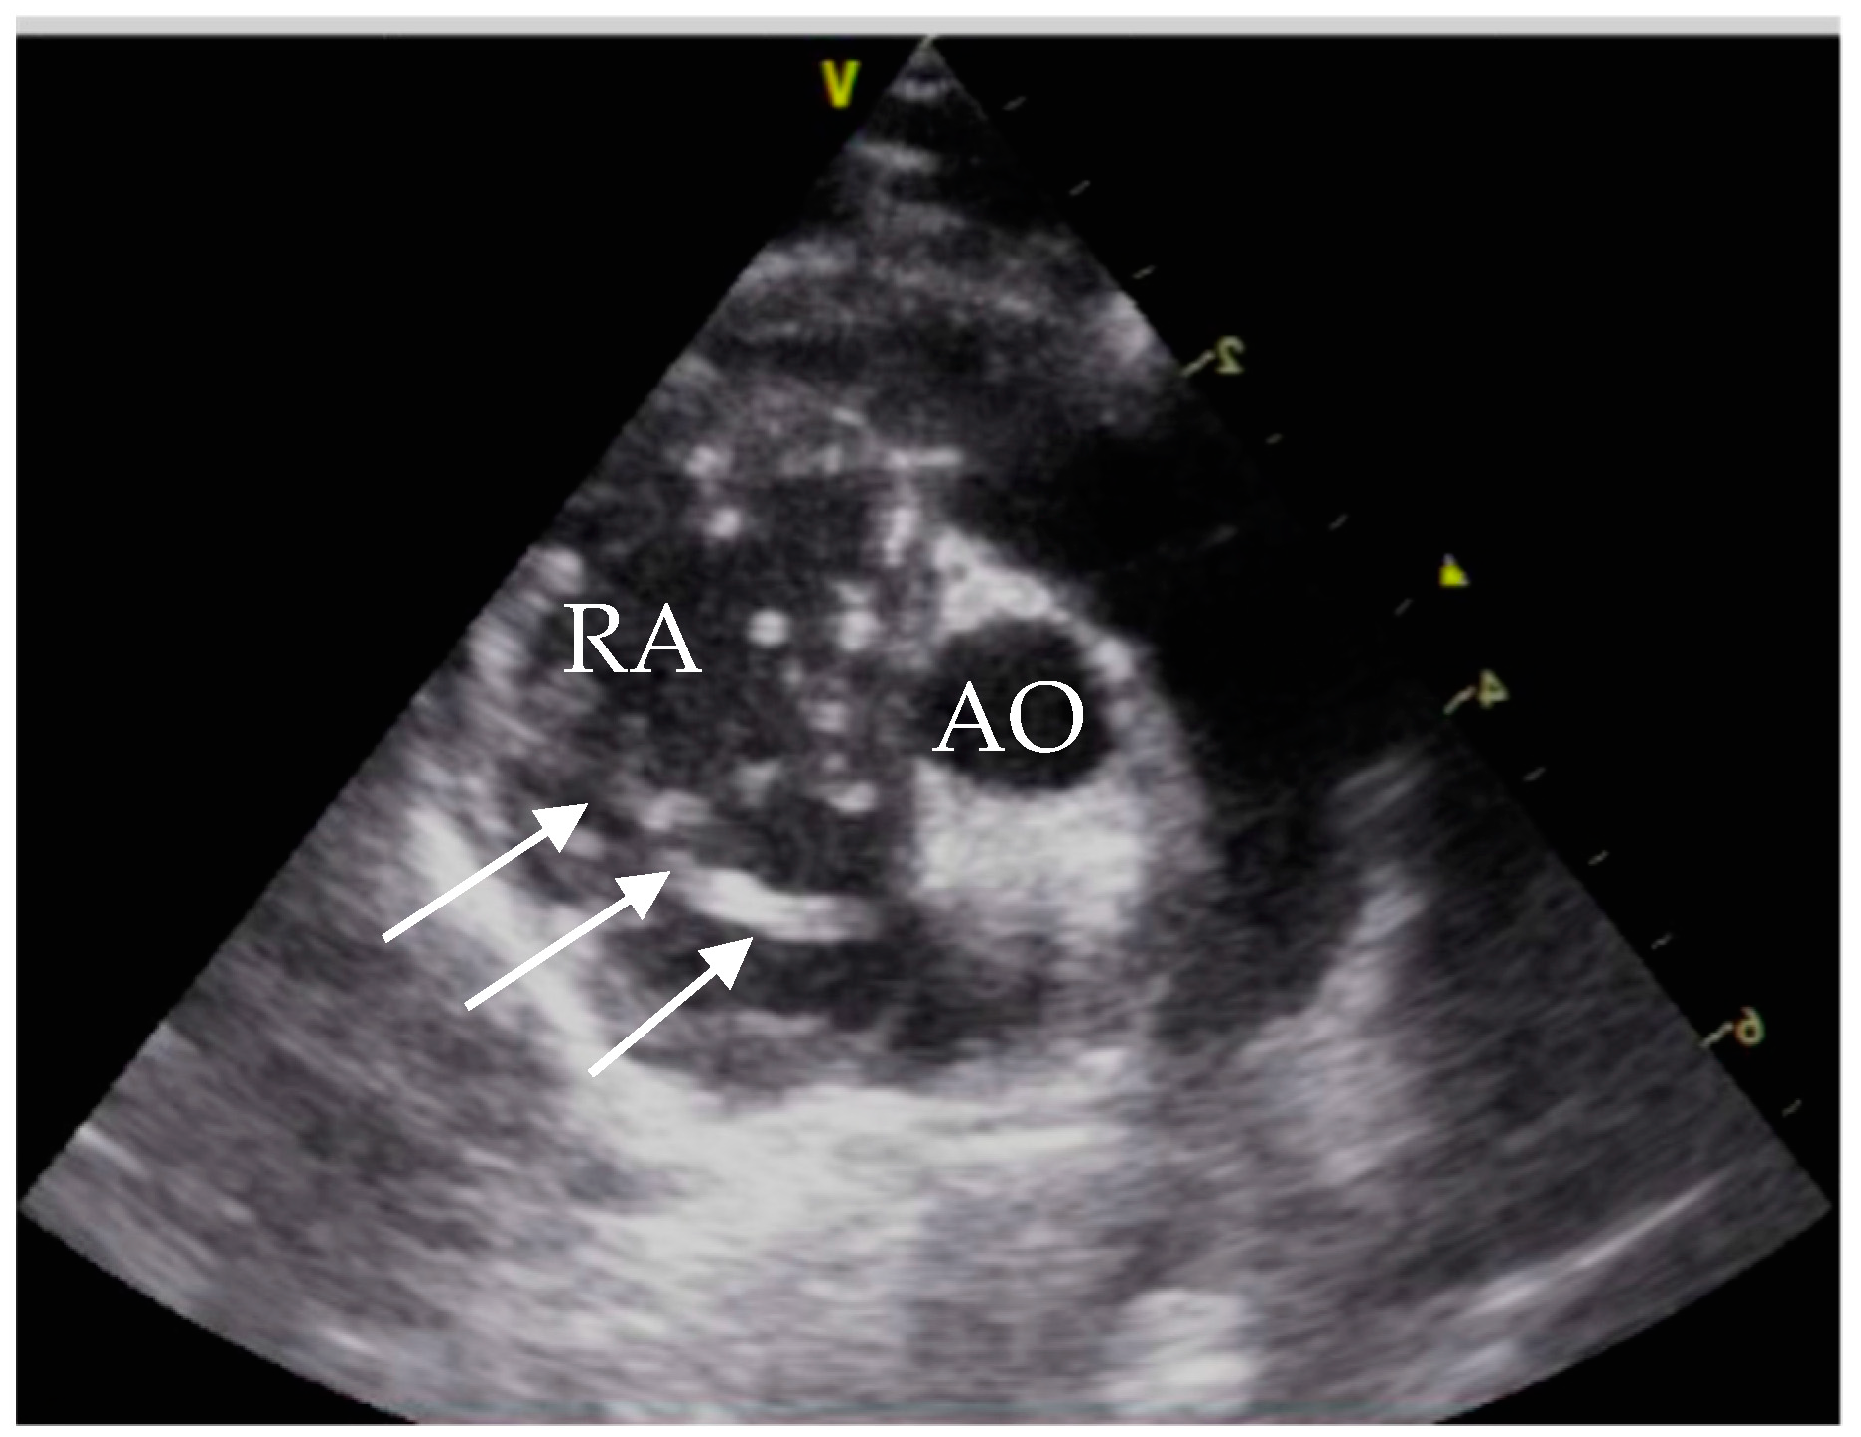

Echocardiographic exams were performed by a single experienced operator with GE vivid™ S6, equipped with a microconvex GE 7s probe. The right atrium showed severe dilatation, and several double lined hyperechoic echoes close the tricuspid valve were seen (Figure 2). The suspected diagnosis based on the echocardiographic findings and the clinical signs was an infection with D. immitis.

Figure 2. Echocardiography showing heartworms, right parasternal short axis view. RA = right atrium; AO = aorta; white arrows = heartworms.

At initial presentation, the cat showed dyspnoea, ascites and double hyperechoic parallel lines in the echocardiography, which is the typical presentation for D. immitis in echocardiography [26]. The sensitivity of echocardiography for detection of D. immitis is operator-dependent and is reported between 88% and 100%. False positive results can be caused by right ventricular chordae tendineae [27].